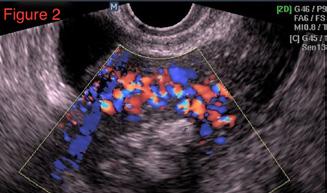

Malformațiile arteriovenoase uterine, provocări de diagnostic și management terapeutic

Conf. Univ. Dr. Mihaela Boț